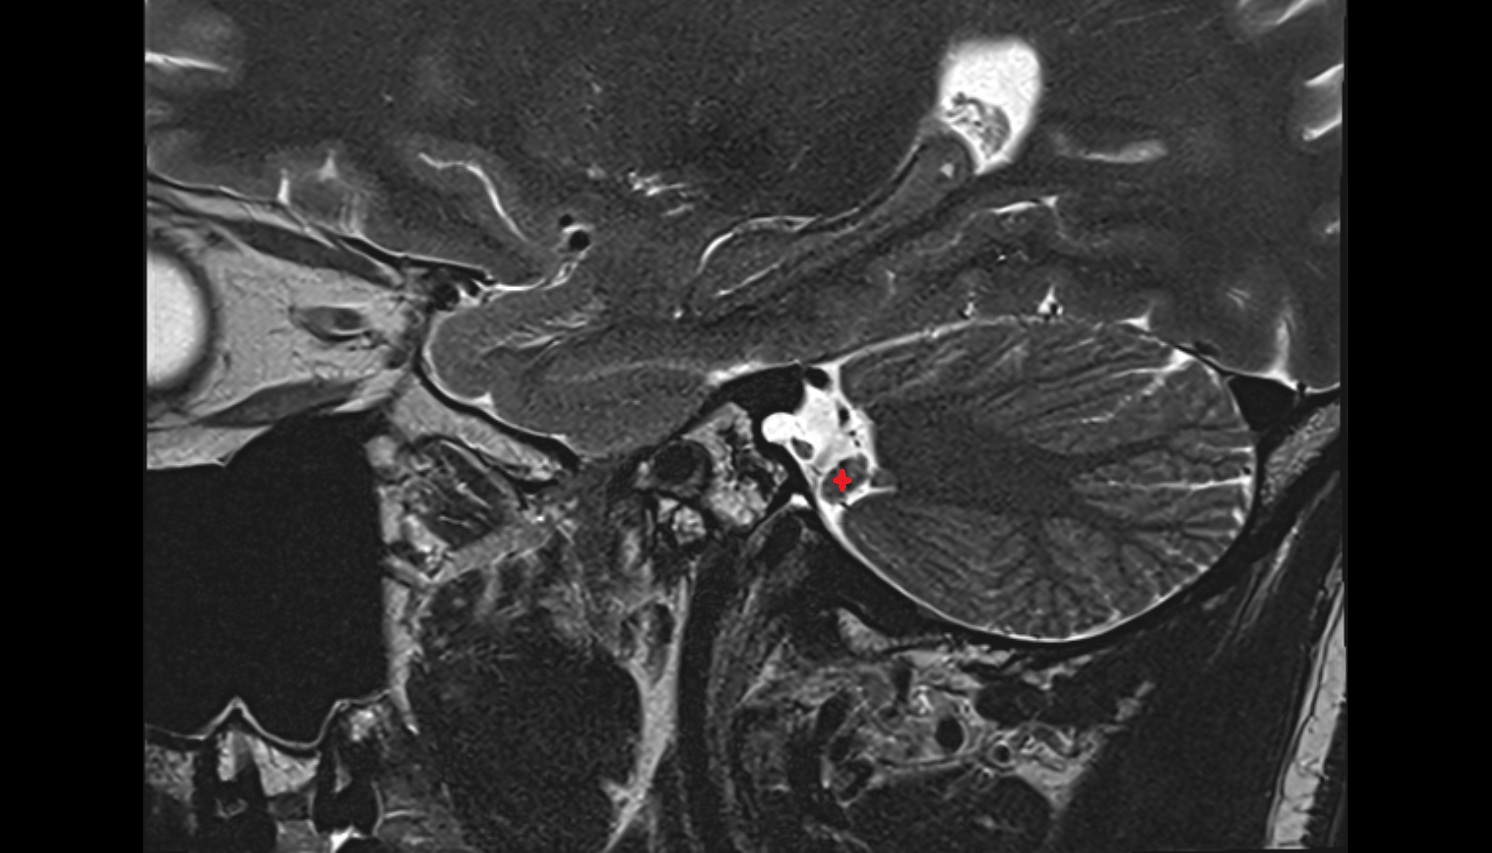

- Temporomandibular joint

- Articular disc of temporomandibular joint

- Intermediate zone of articular disc

- Superior retrodiscal layer

- Articular eminence

- Mandibular condyle

- Mandibular fossa

- Attachment of inferior head of lateral pterygoid muscle

- Attachment of superior head of lateral pterygoid muscle

- Superior head of lateral pterygoid muscle

- Inferior head of lateral pterygoid muscle